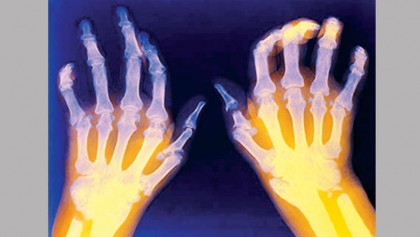

Rheumatoid arthritis facts

While early symptoms of rheumatoid arthritis can actually be mimicked by other diseases, the symptoms are very characteristic of rheumatoid disease. Rheumatoid…